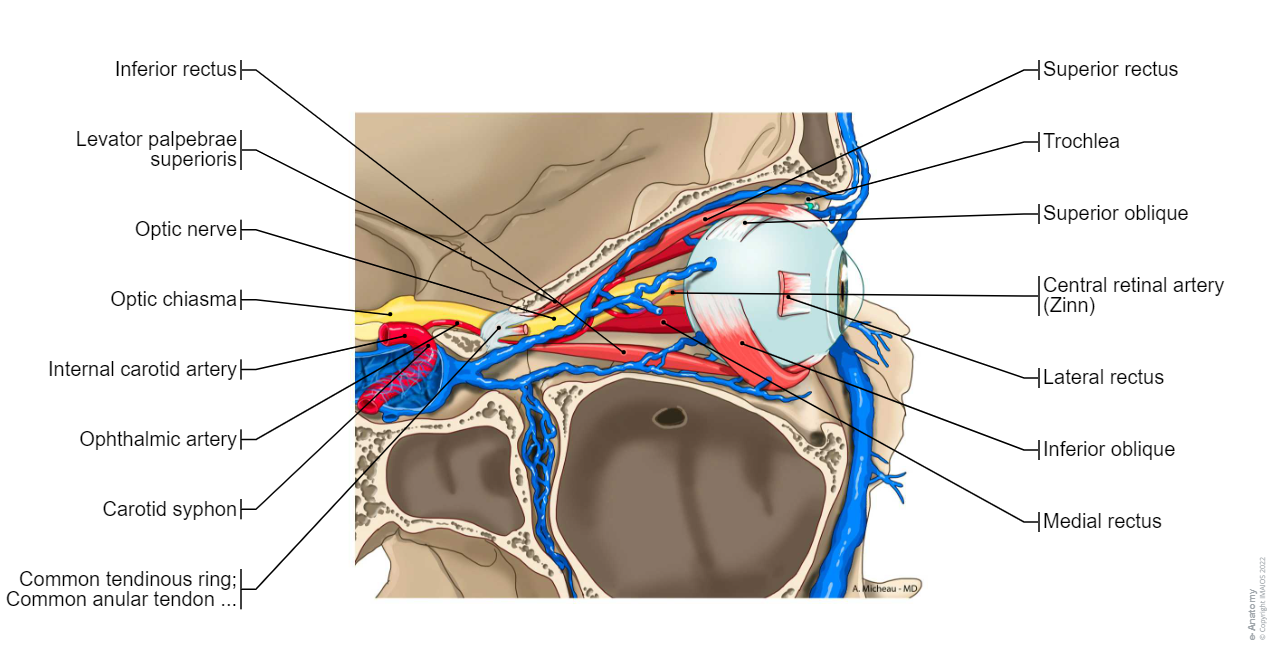

Extraocular muscles; Extrinsic muscles of eyeball: Superior rectus, Inferior rectus, Medial rectus, Superior oblique, Trochlea, Inferior oblique

Extraocular muscles; Extrinsic muscles of eyeball